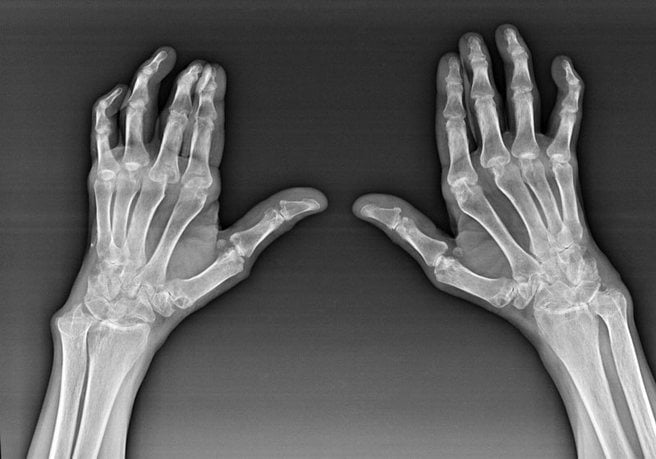

Особенности клинико-рентгенологической картины лежат в основе классификации артроза кистей. Всего выделяют 3 стадии патологии, для каждой из которых характерны определенные симптомы и рентгенологические признаки. Также общепринята классификация артроза Kellgren и Lawrence. Эти авторы выделяют 0 стадию заболевания, при которой рентгенологические признаки поражения костей и хрящей отсутствуют, а клинические проявления выражены слабо.

При артрозе кистей на первой стадии изменяется состав синовиальной жидкости. В ней содержится недостаточное для нормального функционирования хрящей количество питательных веществ. На полученных рентгенографических изображениях отмечается нечеткое сужение суставной щели, формирование начальных остеофитов на краях костных структур.

На рентгенографических снимках отчетливо визуализируются множественные остеофиты, субхондральный остеосклероз в костных тканях, заметное сужение суставной щели.

При проведении рентгенологического исследования выявляются обширные остеофиты, полное или частичное сращение суставной щели, субхондральные кисты, «суставные мыши» (свободно перемещающиеся твердые частицы). Суставная площадка сильно деформирована, что приводит к нарушению соотношения между анатомическими структурами. В дегенеративный процесс оказываются вовлечены связки и сухожилия — они укорачиваются, становятся менее прочными.